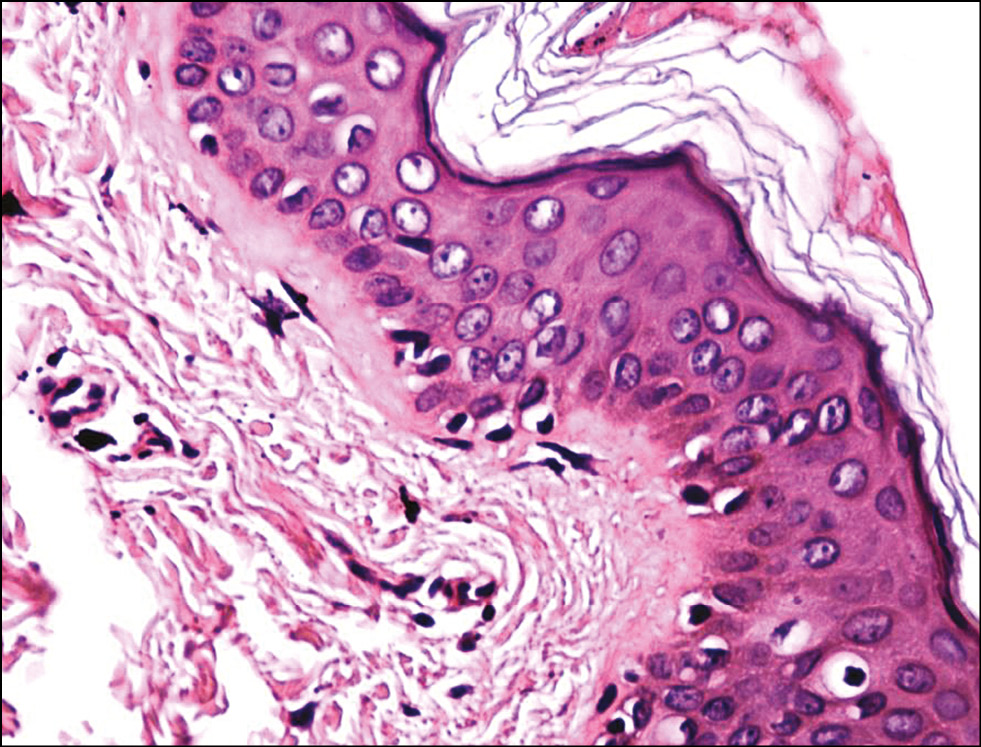

Рис. 7. Гистологическая картина кожи заушной области женщины через 3 дня после фотодинамической терапии. Окраска гематоксилином и эозином, x400.

Fig. 7. Histological picture of the skin behind the ear of women 3 days after photodynamic therapy. Hematoxylin and eosin staining, x400.

Подэтап 2А. Гистологическое исследование показало, что сразу после воздействия ФДТ (рис. 6) в коже обнаруживались единичные лейкоциты в толще эпидермиса и на его поверхности; ядра клеток эпидермиса и их цитоплазма на данном участке были набухшие, сосочки дермы несколько сглажены, рыхлая волокнистая соединительная ткань сосочкового слоя дермы отёчна. На третий день (рис. 7) после процедуры отмечено уменьшение количества набухших ядер в эпидермисе, заметны мелкоочаговые кровоизлияния в сетчатом слое дермы с перифокальной сосудистой реакцией и слабовыраженным отёком сетчатого слоя дермы. Спустя 20 дней (рис. 8) после воздействия заметна умеренная пролиферация клеток эпидермиса и дермы. Отмечается уплотнение коллагеновых волокон сетчатой дермы. Патологических изменений в эпидермисе, дерме, придатках кожи не обнаружено.